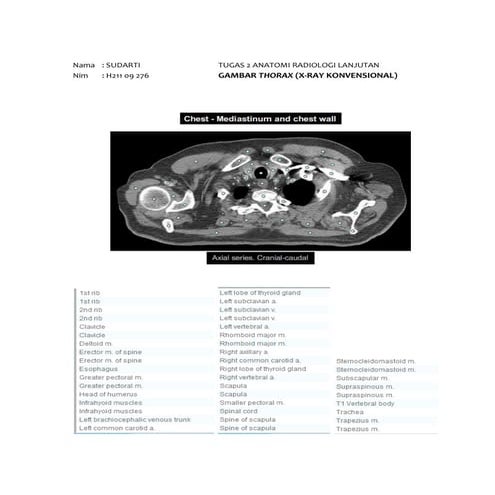

X ray (kel x)